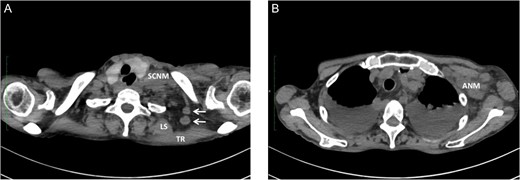

We have had three cases of this unusual LNM from cancer of the thoracic esophagus to date. Clinicopathological characteristics and survival are presented in Table 1. This unusual LNM developed after esophagectomy in two patients (cases 1 and 2, Fig. 2) and was found at presentation in a third patient (case 3, Fig. 3).

Undifferentiated carcinoma was confirmed by excisional biopsy of the tumor located between TR and LS (arrow).